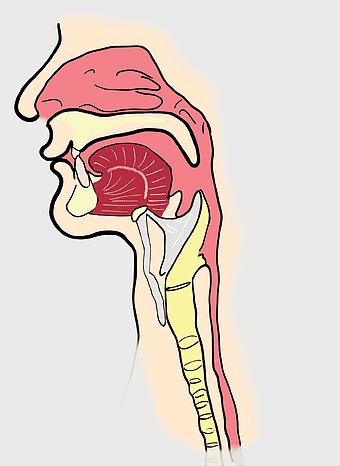

Bronchus, Trachea, Larynx, respiratory tract anatomy, pulmonary system diagram, medical illustration, airway structure analysis -

Pharynx anatomy, Otorhinolaryngology diagram, Throat larynx illustration, Sinus infection symptoms, Respiratory system, Head and neck medical, Upper airway structure -